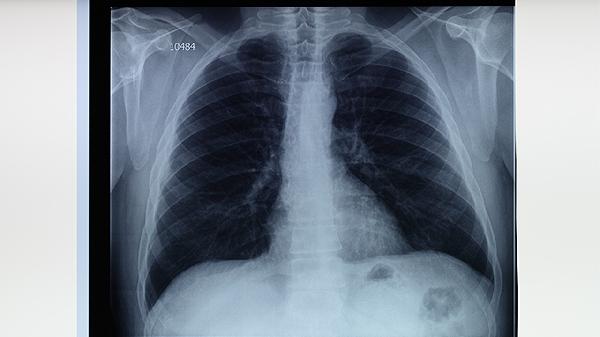

结核菌素试验阴性者若存在持续咳嗽、低热、盗汗等结核病可疑症状,建议进行胸部X线检查、痰涂片抗酸染色或γ-干扰素释放试验等补充检测。日常应注意保持室内通风,避免与活动性肺结核患者密切接触,保证充足营养摄入以维持正常免疫功能。